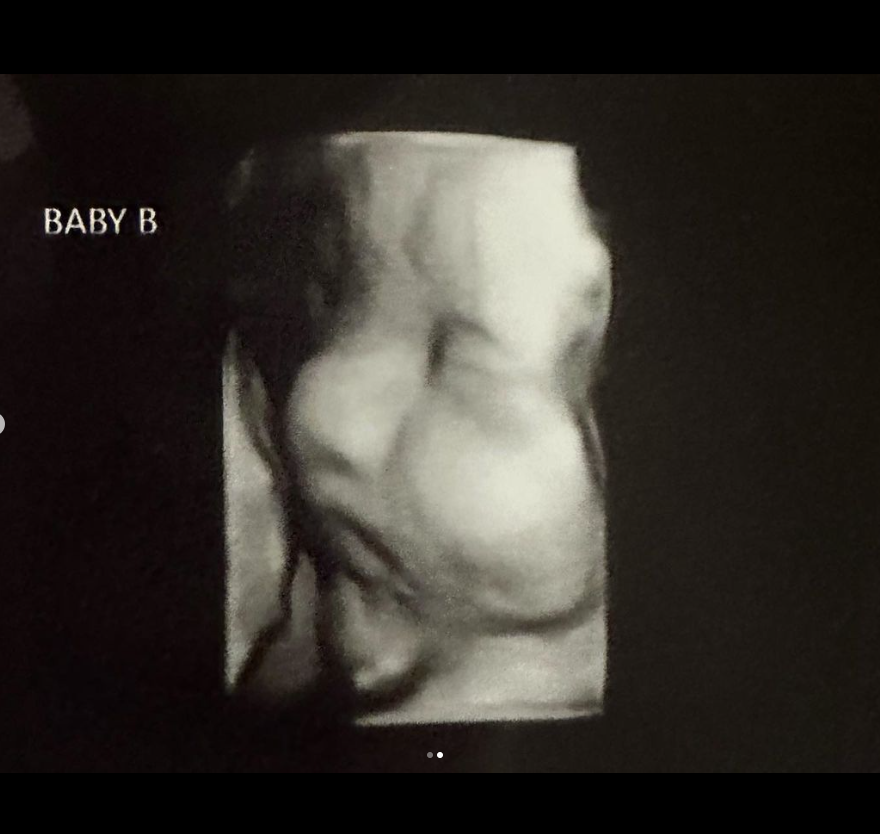

Screenshot des zur Verfügung gestellten Ultraschallbildes ©doubleuhatchlings, Kelsey Hatcher